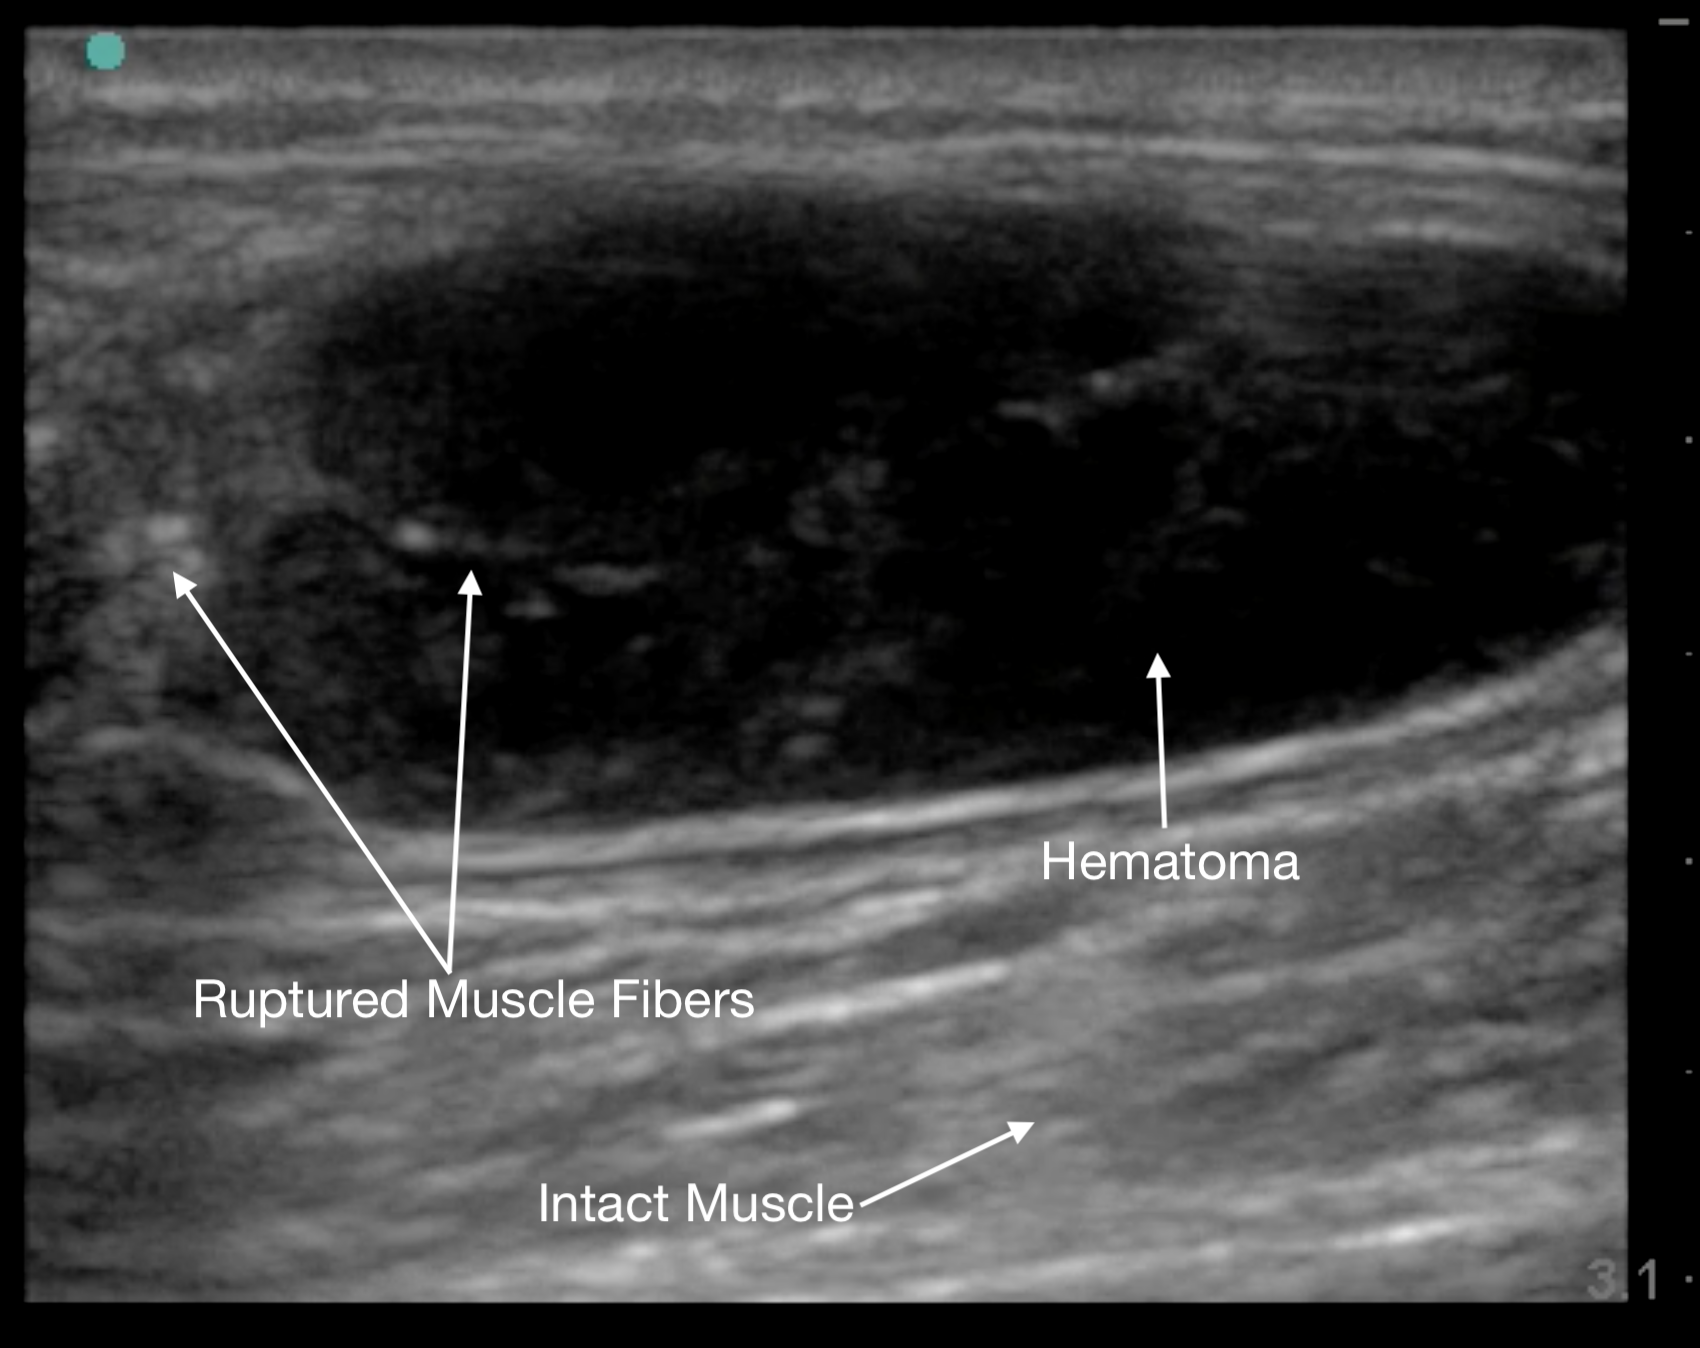

Muscle tears in biceps femoris, rectus femoris, and gastrocnemius will show a discontinuity in the muscle belly and adjacent hematoma. The associated “clapper in bell” sign is the retracted upper portion of torn muscle fibers (clapper) surrounded by hematoma (bell).19

Figure 12.

Gastrocnemius muscle tear in short axis at its proximal end.